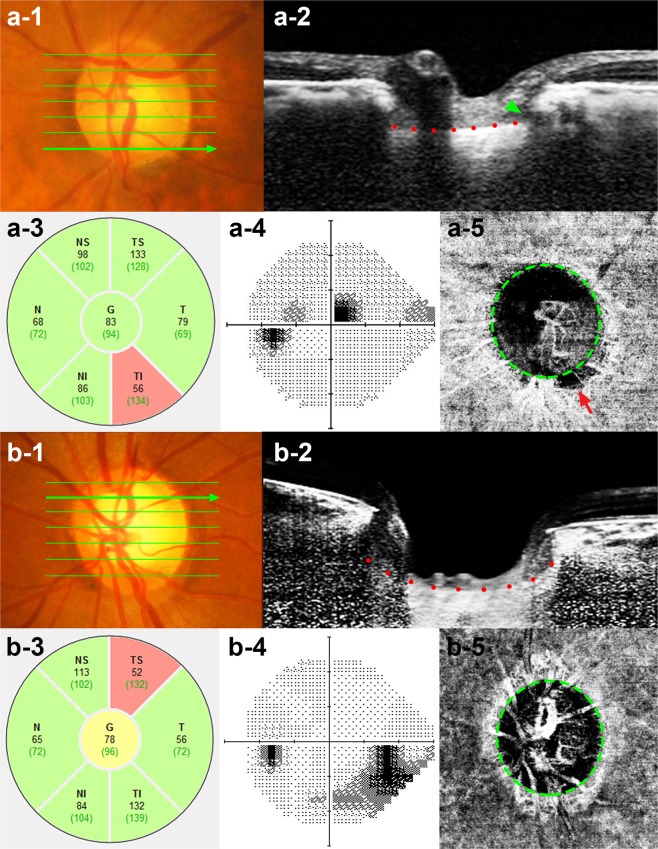

Representative cases

Representative cases showing the differences in LCCI in eyes with and without focal LC defects are presented in Fig. 2. LC curvature was considerably smaller in the eye with (Fig. 2a) than without (Fig. 2b) focal LC defect.

Figure 2.

Representative eyes with (a) and without a (b) a focal LC defect. (a-1, b-1) Disc photographs of the left eye of a 75-year-old man (a), and a 50-year-old woman (b). (a-2, b-2) B-scan images obtained at the locations indicated by the green arrows in a-1and b-1, respectively. The focal LC defect is indicated by the green arrow head (b-2). Note that LCCI was smaller in the eye with (a-2, red dots) than without (b-2, red dots) a focal LC defect. However, retinal nerve fiber layer thickness (a-3, b-3) and visual field damage (a-4, b-4) did not differ between these two eyes. (a-5, b-5) Green dashed lines indicate the optic disc margin, and the red arrow indicates MvD (a-5). Note that the parapapillary MvD was located at the same sector as the focal LC defect.